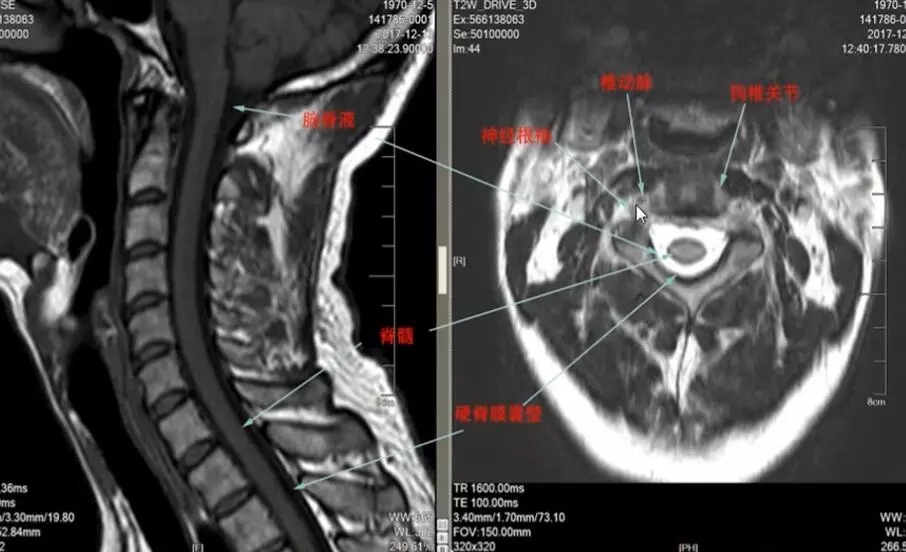

扫颈椎mr经常可以看到椎动脉